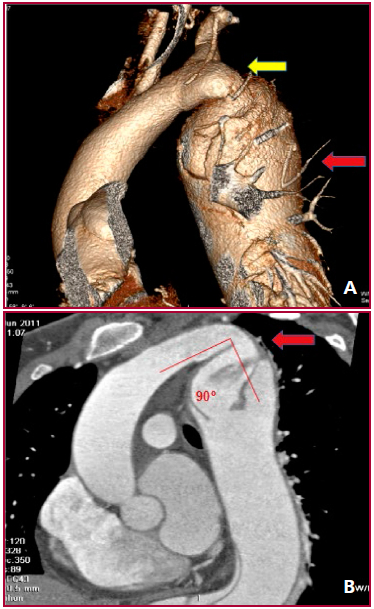

Se realizó una angio-tomografia (angio-TC) que constató: recoartación aórtica distal a la subclavia izquierda, asociada a un aneurisma disecante de aorta descendente (52 mm) que llegaba al flap hasta ambas ilíacas, con flujos viscerales conservados (Figura 1A).

Debido a la angulación aórtica de 90° en el arco aórtico distal, sumada a la hipoplasia poscoartación, se descartó la opción endovascular (Figura 1B).